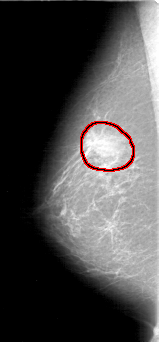

FILE: D_4070_1.RIGHT_MLO.OVERLAY

TOTAL_ABNORMALITIES 1

ABNORMALITY 1

LESION_TYPE MASS SHAPE OVAL MARGINS OBSCURED

ASSESSMENT 0

SUBTLETY 4

PATHOLOGY BENIGN

TOTAL_OUTLINES 1

BOUNDARY